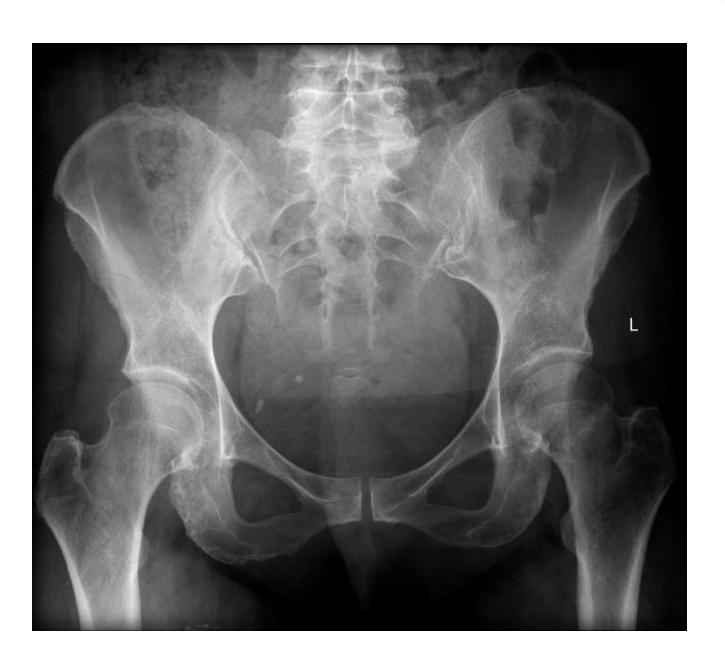

A teenager with acute onset of pain in the right hip during a run. He sustained the injury seen in the x-rays with a white arrow. This injury usually occurs due to a forceful eccentric contraction of which of the following muscles?

- C. Rectus femoris

- Sartorius

Pelvic Anatomy

Which of the following muscles is attached to the structure pointed by the arrow?

- C. Sartorius

Note: Arrow was pointing at ASIS (Anterior Superior Iliac Spine)